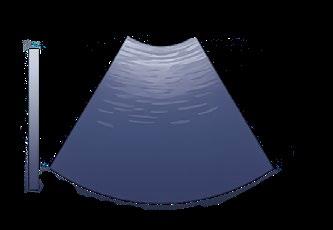

La ecografía pulmonar tiene un interés creciente en el sector ganadero. De hecho, en bovino su uso ya está extendido en algunas fases del ciclo productivo, como por ejemplo, en la recría de terneras de aptitud lechera o en las incorporaciones a granjas de cebo de terneros.

Ahora, esta técnica empieza a cobrar relevancia también en ovino, especie en la que las enfermedades respiratorias tienen un notable impacto sanitario y productivo.

El pulmón de la oveja tiene buena capacidad para transmitir el ultrasonido, lo que permite en adultos usar frecuencias intermedias entre 5,0 y 6,5 MHz.

En corderos jóvenes o al explorar estructuras más superficiales, puede ser útil emplear frecuencias más altas para mejorar la resolución de la imagen (hasta 10 MHz).

Para este tipo de examen, se pueden utilizar sondas convex o microconvex, ya que su forma curva y su imagen trapezoidal facilitan el acceso entre las costillas y ofrecen buena visualización. También es válida la sonda lineal para ovejas de mayor tamaño.

Los ovinos tienen 13 pares de costillas, por tanto, poseen 12 espacios intercostales y, para examinar los primeros espacios intercostales, se recomienda extender la extremidad anterior del animal hacia delante para facilitar el acceso a esa región.

El examen ecográfico se realiza con la oveja en estación, colocando la sonda de forma paralela a las costillas.

El ajuste inicial de profundidad en 6 cm suele ser adecuado para un estudio torácico estándar.

Es importante examinar ambos lados del tórax, ya que las lesiones pueden ser unilaterales o variar en severidad.

PULMÓN SANO

En un pulmón sano, se observa una línea hiperecogénica continua en la región superior, correspondiente a la pleura visceral, que representa la interfaz con la superficie pulmonar.

Al ser un órgano predominantemente aireado, el pulmón genera artefactos de reverberación conocidos como líneas A, que aparecen como líneas horizontales paralelas y son un hallazgo ecográfico normal.

Esta imagen puede variar según la edad o el estado corporal del animal.

PULMÓN ALTERADO

Entre las alteraciones más comunes se encuentran las líneas B o "colas de cometa", que indican inflamación o líquido en el tejido.

Pueden observarse irregularidades, engrosamientos o discontinuidades pleurales, sugestivas de infección, así como consolidaciones pulmonares, donde el tejido pierde su patrón aireado y se vuelve más denso.

Las consolidaciones pulmonares pueden ser localizadas o extensas y, en casos graves, pueden dar un aspecto similar al hígado (hepatización), característico de neumonías avanzadas.

Dentro de estas zonas es frecuente visualizar un broncograma aéreo, representado por bronquios llenos de aire como puntos o líneas hiperecogénicas.

La ecografía torácica se realizó con un ecógrafo portátil (Esaote MyLab One Vet) equipado con sonda microconvexa de 10 MHz. En esta, se evaluaron secuencialmente los lóbulos pulmonares craneales, medios y caudales, categorizando las imágenes obtenidas según la aparición de:

Líneas A (patrón normal) (Imagen 2a).

Líneas B (Imagen 2b).

Consolidaciones (Imagen 2c).

Derrame pleural.

Abscesos (Imagen 2).